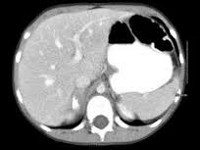

С целью визуализации ганглионейробластомы применяется МСКТ или УЗИ органов брюшной полости, КТ органов грудной клетки, пневмомедиастинография, МРТ головного мозга. Для обнаружения метастазов опухоли применяется рентгенография и сцинтиграфия скелета, УЗИ печени, пункционная биопсия лимфатического узла и пр.